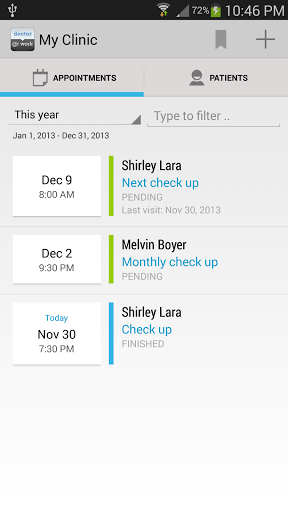

Gérez les dossiers médicaux et de santé de vos patients, rendez-vous et consultez les notes facilement.

Cette application est utile pour les professionnels médicaux et de la santé qui visitent les patients de temps en temps et a besoin d'un moyen de garder une trace des dossiers médicaux. C'est une application pratique que vous pouvez apporter chaque fois que vous faites votre pratique médicale.

• Voir la visite du patient / antécédents médicaux